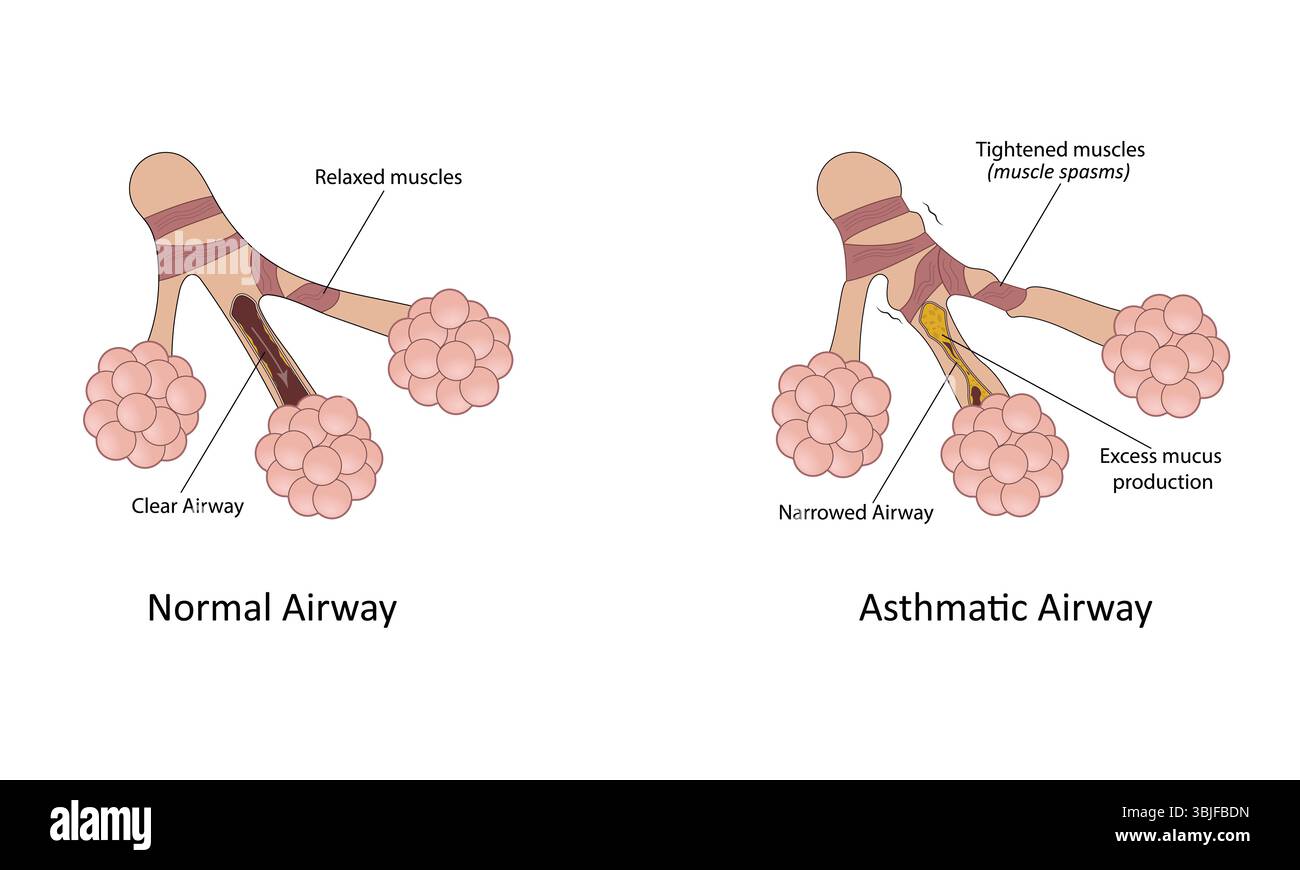

Bronchiectasis. Normal airway and asthmatic airway Stock Photohttps://www.alamy.com/image-license-details/?v=1https://www.alamy.com/bronchiectasis-normal-airway-and-asthmatic-airway-image456325897.html

Bronchiectasis. Normal airway and asthmatic airway Stock Photohttps://www.alamy.com/image-license-details/?v=1https://www.alamy.com/bronchiectasis-normal-airway-and-asthmatic-airway-image456325897.htmlRF2HEBC9D–Bronchiectasis. Normal airway and asthmatic airway

Asthma vector illustration Stock Vectorhttps://www.alamy.com/image-license-details/?v=1https://www.alamy.com/asthma-vector-illustration-image682606449.html

Asthma vector illustration Stock Vectorhttps://www.alamy.com/image-license-details/?v=1https://www.alamy.com/asthma-vector-illustration-image682606449.htmlRF3BJFBDN–Asthma vector illustration